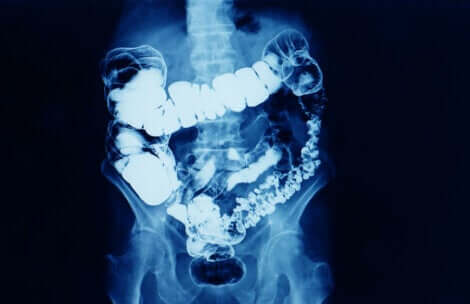

O glicerol é o ingrediente ativo dos supositórios de glicerina. É uma substância que exerce sua ação laxante quando administrada por via retal. Esse efeito é obtido porque, quando os supositórios são administrados, as fezes amolecem e produzem um leve efeito irritante local, estimulando o peristaltismo intestinal.

- Efeito irritante local na mucosa retal, mas esse efeito não afeta as paredes intestinais. Sua ação faz com que o reto se contraia, favorecendo a expulsão das fezes.

- Efeito osmótico: o glicerol tem a propriedade de absorver água e isso, junto com suas propriedades lubrificantes, amolece as fezes e facilita a sua expulsão.

O efeito dos supositórios de glicerina se manifesta de 15 minutos a uma hora após a sua aplicação. Além disso, o glicerol não é absorvido e é quase totalmente eliminado com as fezes.